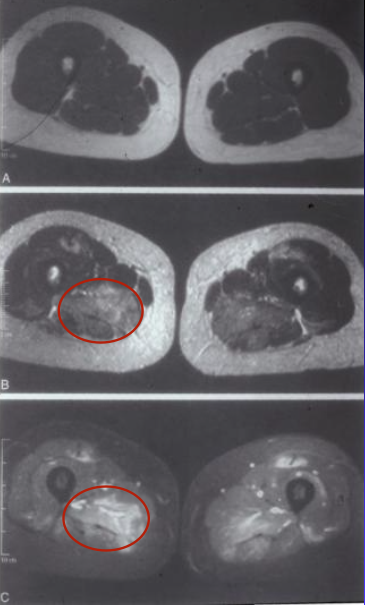

MRI shows increased edema in affected area of muscle - marker of inflammation

endomysial inflammation w/ predominantly CD8 T cells in polymyositis

perimysial inflammation w/ CD4 T cells in dermatomyositis